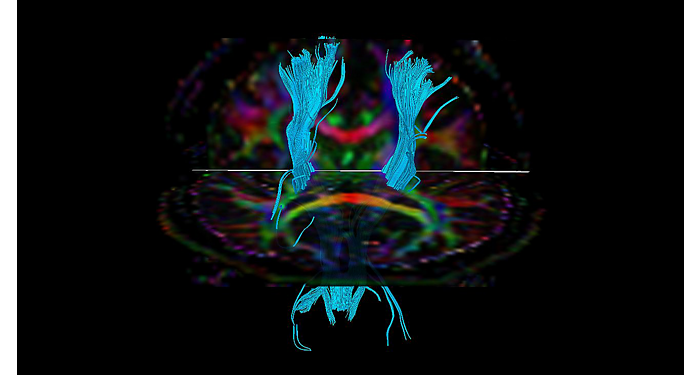

El 70% de los radiólogos consideran que las indicaciones neurológicas son un desafío, sobre todo debido a la falta de técnicas apropiadas de imagenología y visualización¹. Philips tiene como objetivo proporcionar la mejor claridad de diagnóstico posible y orientación terapéutica para todos los pacientes con trastornos neurológicos. Al aprovechar nuestra plataforma digital dStream, este año presentamos un conjunto de estrategias nuevas de imagenología y visualización. Esto puede ayudarlo a resolver preguntas sobre neurología complejas con mayor certeza, así como a desbloquear nuevos territorios neurológicos en aplicaciones neurofuncionales avanzadas. Este es un paso clave para aumentar el diagnóstico neurológico y, en última instancia, impactar más vidas con la RM. ¹ TMTG Market Survey 2016

Nuevas aplicaciones neurológicas